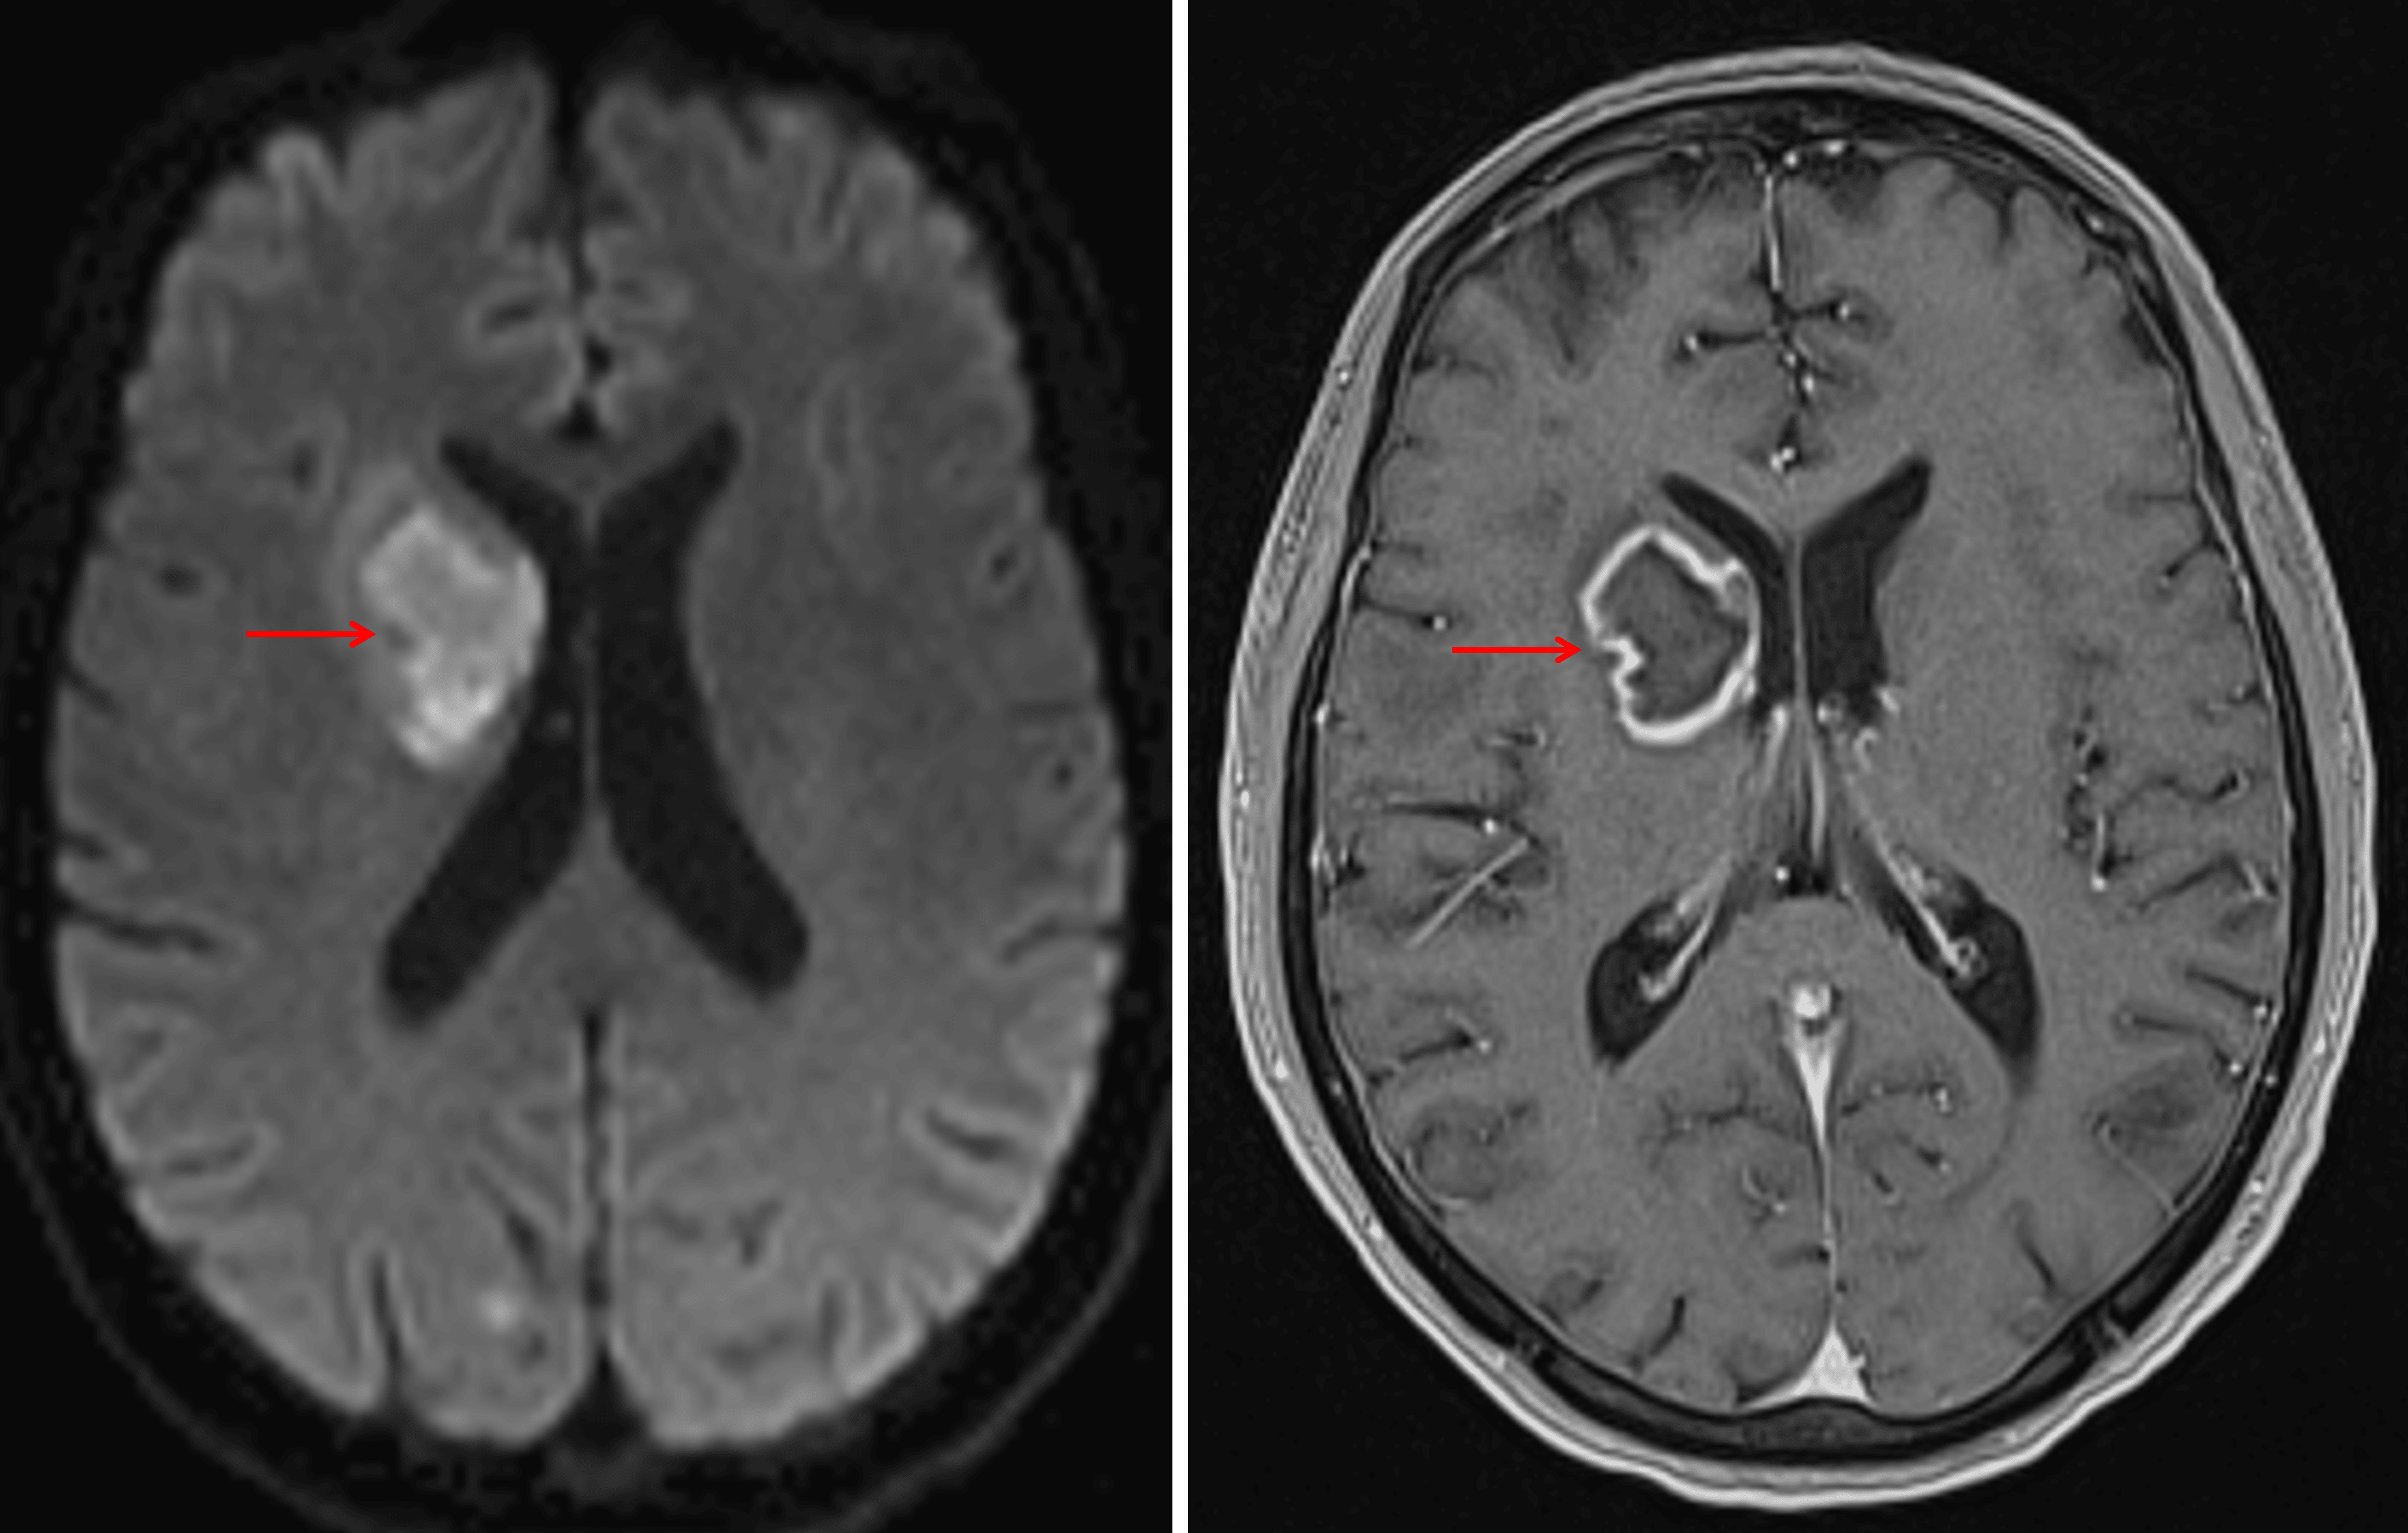

Peripherally-enhancing lesion with central restricted diffusion in the right basal ganglia and internal capsule (red arrows), highly concerning for a pyogenic abscess. Close proximity to the ventricular margin increases the risk for ventriculitis.

Enhancement extending along the superior margin of the right lateral ventricle (red arrow), which raises concern for developing ventriculitis.